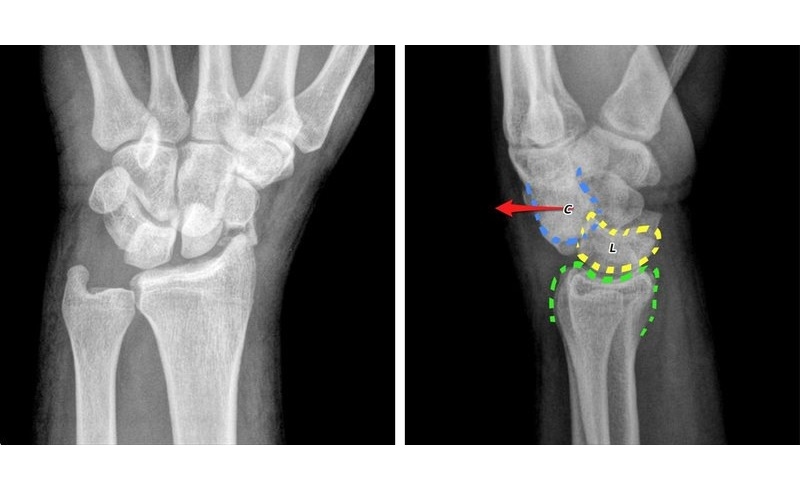

Cổ tay là một cấu trúc phức tạp, gồm 8 xương nhỏ có hình dạng khác nhau như hình vuông, hình bầu dục và hình tam giác, liên kết với hai xương dài của cẳng tay là xương quay và xương trụ. Kỹ thuật chụp X – quang cổ tay giúp hiển thị rõ cấu trúc giải phẫu này thông qua hình ảnh với các sắc độ xám khác nhau.

Phương pháp chụp X – quang sử dụng bức xạ điện từ để tạo ra hình ảnh bên trong cơ thể. Khi chùm tia X đi qua vùng cổ tay, các mô mềm sẽ hấp thụ ít bức xạ và hiển thị trên phim với màu xám, trong khi canxi trong xương hấp thụ nhiều bức xạ hơn nên cho hình ảnh màu trắng rõ nét. Đây là kỹ thuật cận lâm sàng không xâm lấn, cho phép bác sĩ đánh giá chính xác tổn thương xương và các bệnh lý liên quan đến vùng cổ tay.